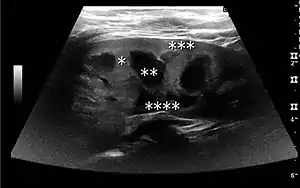

Figure 7. Advanced polycystic kidney disease with multiple cysts.[1]

Complex cysts can have membranes dividing the fluid-filled center with internal echoes, calcifications or irregular thickened walls. The complex cyst can be further evaluated with Doppler US, and for Bosniak classification and follow-up of complex cysts, either contrast-enhanced ultrasound (CEUS) or contrast CT is used (Figure 6). The Bosniak classification is divided into four groups going from I, corresponding to a simple cyst, to IV, corresponding to a cyst with solid parts and an 85–100% risk of malignancy.[1] In polycystic kidney disease, multiple cysts of varying size in close contact with each other are seen filling virtually the entire renal region. In advanced stages of this disease, the kidneys are enlarged with a lack of corticomedullary differentiation (Figure 7).[1]